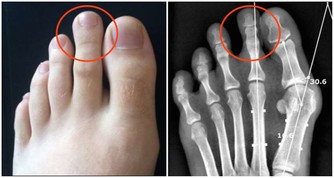

4、易生病,抵抗力下降: 我們生活的環境中,無處不存在著看不見的細菌病毒,因為身體擁有強大的免疫力才使我們免受這些病菌的感染。但長期生活在甲醛超標的環境會使免疫系統遭受破壞,降低人體抵抗力,不能有效地防禦外界病原微生物的侵入,從而導致疾病發生。家人入住新居後經常感冒,尤其是老人兒童,感冒後一個星期也不見好轉,這都可能是甲醛超標引起的。